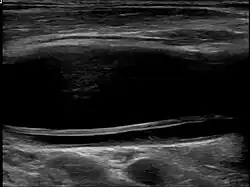

-

Carotid artery dissection -

Dissection of the carotid artery on ultrasound